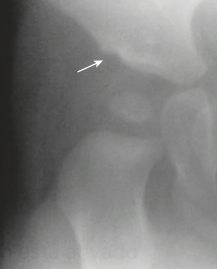

Principal alteração radiográfica

Achado radiográfico com obliquidade aumentada e perda da concavidade acetabular.

Q

Incluem redução inadequada, displasia residual do fêmur e do acetábulo, e necrose avascular da cabeça femoral.

Sinais radiográficos tardios

Desenvolvimento de osteoartrite e subluxação do quadril.